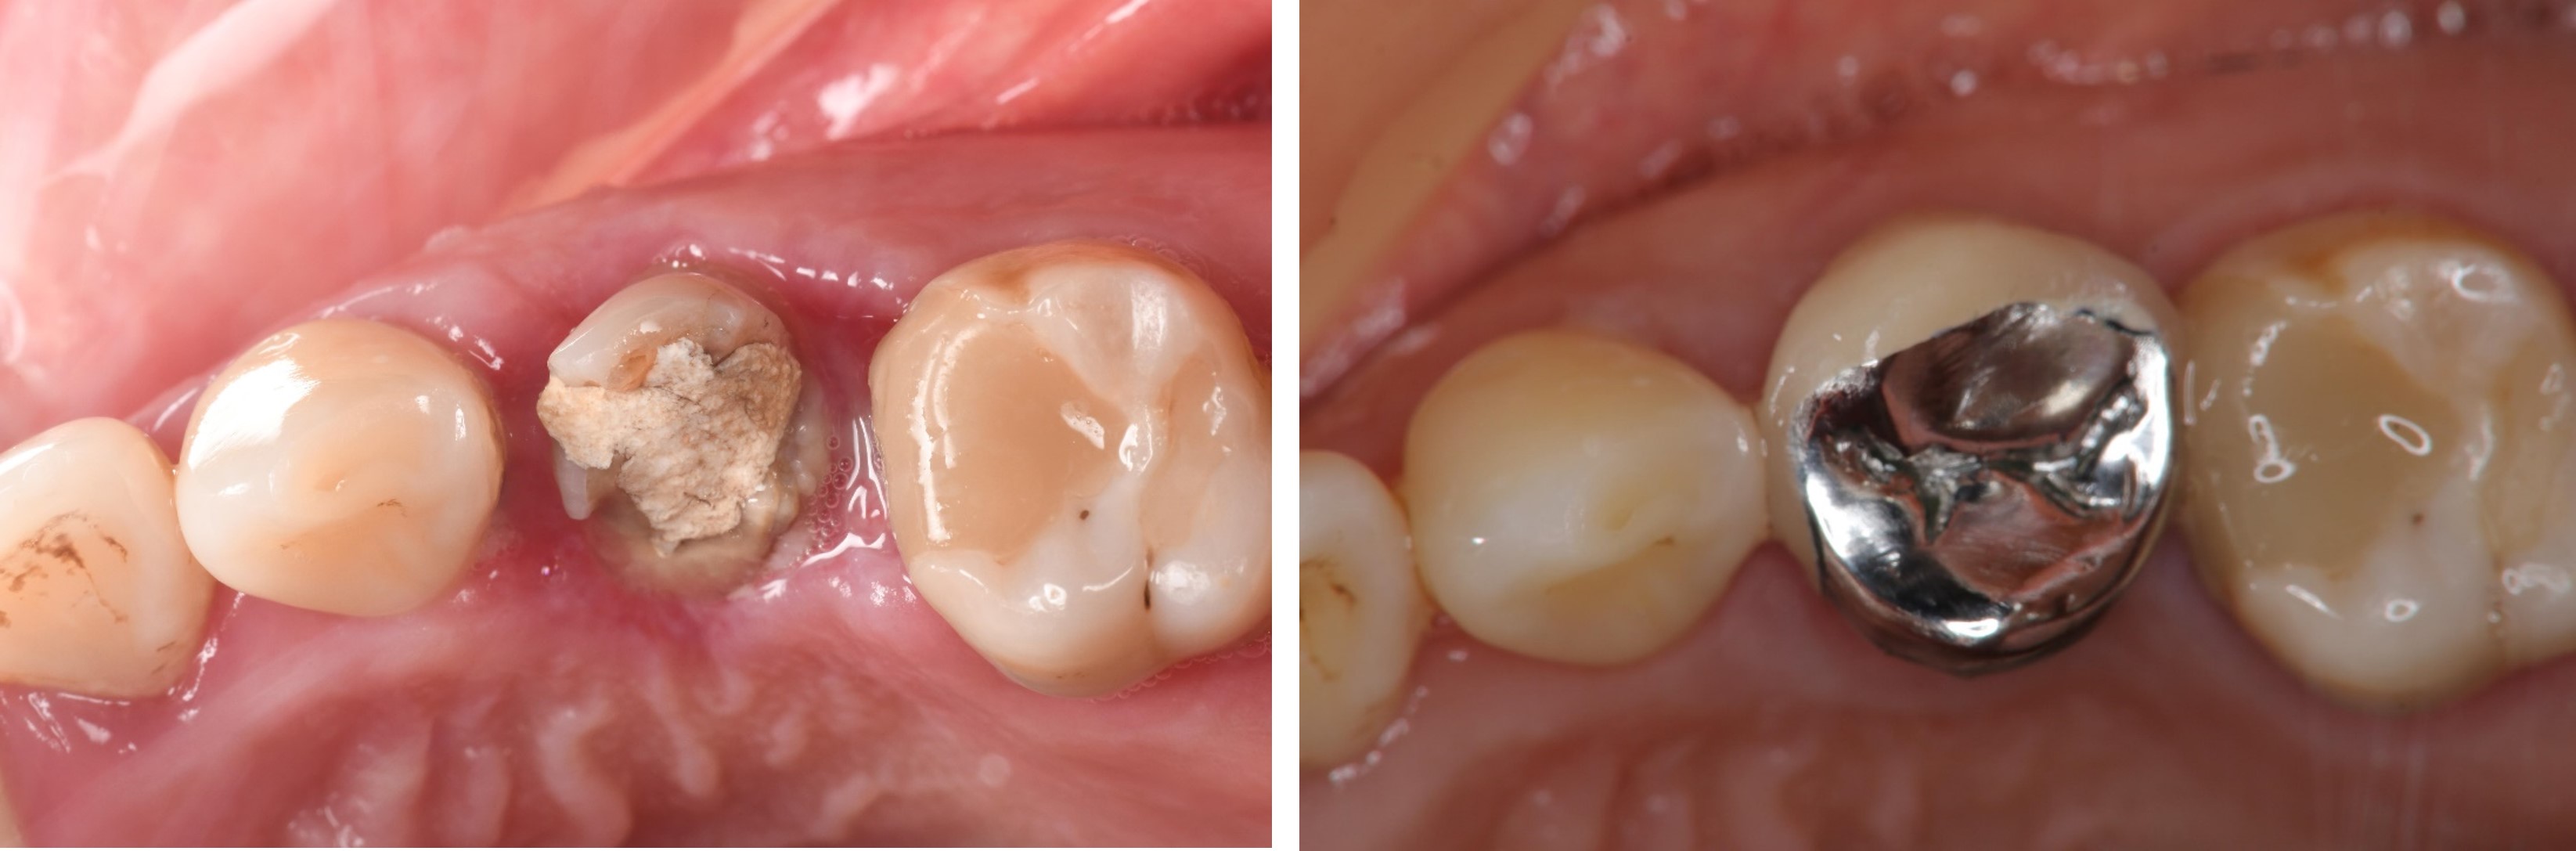

膺復前評估牙齦、牙齒狀態

治療後,咬合良好

治療後,密合度良好

術前、術後比較